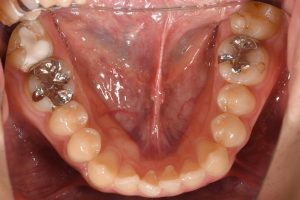

治療前